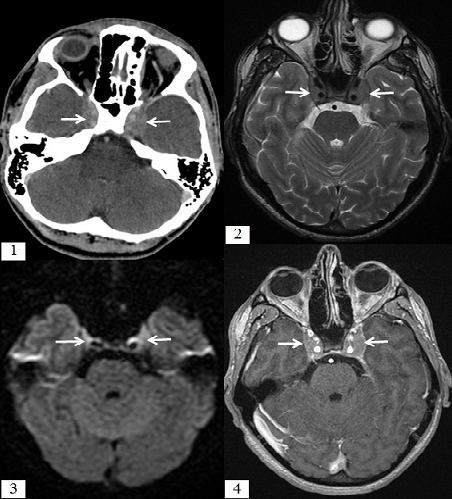

L'atteinte du sinus caverneux au cours des leucémies aigues est rare et peut se faire par extension directe ou via une dissémination hématogène.L'aspect en imagerie n'est pas pathognomonique mais reste évocateur : le scanner montre une infiltration tissulaire du sinus caverneux, l'IRM est plus performante montrant un hypo signal T2 de cette infiltration, avec restriction de la diffusion et prise de contraste après injection du Gadolinium. Nous rapportons le cas d'un jeune homme, âgé de 22 ans, admis aux urgences dans un tableau d'HTIC évoluant depuis 10 jours avec diplopie horizontale. Une TDM cérébrale a objectivé un aspect élargi des 2 sinus caverneux qui sont spontanément hyperdense rehaussés de façon modérée après injection du produit de contraste. La NFS a montré une thrombopénie avec un taux de plaquettes à 33000/mm3, une hyperleucocytose à 16700/mm3, le taux d'hémoglobine était à 13.7g /l. Nous avons complété le bilan d'imagerie par une IRM cérébrale qui a montréune infiltration tissulairedes 2 sinus caverneux se présentant en hypo signal T2, avec restriction de la diffusion et prise de contraste homogène après injection du gadolinium. Une atteinte lymphomateuse a été évoquée sur cet aspect. 2 jours après le patient a présenté des hématomes à chaque point d'injection. Une NFS avec frottis ont montré un taux de plaquettes à 21 000/mm3 et des blastes à 25%, ensuite un myélogramme a été réalisé revenant en faveur d'une leucémie aigue lymphoblastique. L'évolution a été fatale par hémorragie digestive.